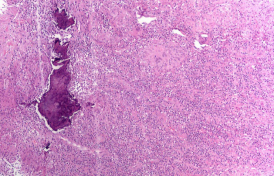

病理提示“左第二近节指骨骨髓炎病灶”:上皮样肉芽肿性病变伴急性炎性坏死和骨质破坏

“右中指病灶+中指骨质破坏组织切除标 本”:符合内生性软骨瘤

手足短骨解剖及常见疾病的影像学表现“左足第一跖骨肿物”:骨巨细胞瘤,肿瘤浸润骨皮质及软组织,伴反应性骨壳形成